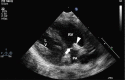

Case report: Two cases suspected to have CINCA syndrome were put on treatment with anakinra in the early neonatal period due to severe clinical presentation. We observed a rapid and persistent decline of clinical signs and systemic inflammation and good drug tolerance. Diagnosis was confirmed in both cases by mutations in the NLRP3/CIAS1-gene coding for cryopyrin. As particular neonatal clinical signs polyhydramnios and endocardial overgrowth are to be mentioned.